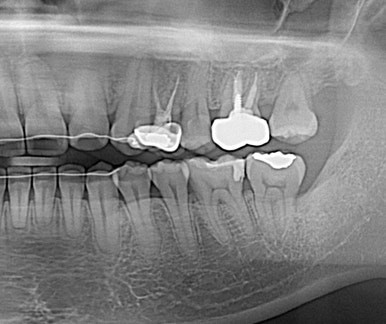

드디어 구강내로 얼굴을 내밀고 제 위치에 안착~

치료 중 임신으로 방사선 사진을 남기지 못해 아쉽지만 기능을 잘해주고 있어 뿌듯하다^^